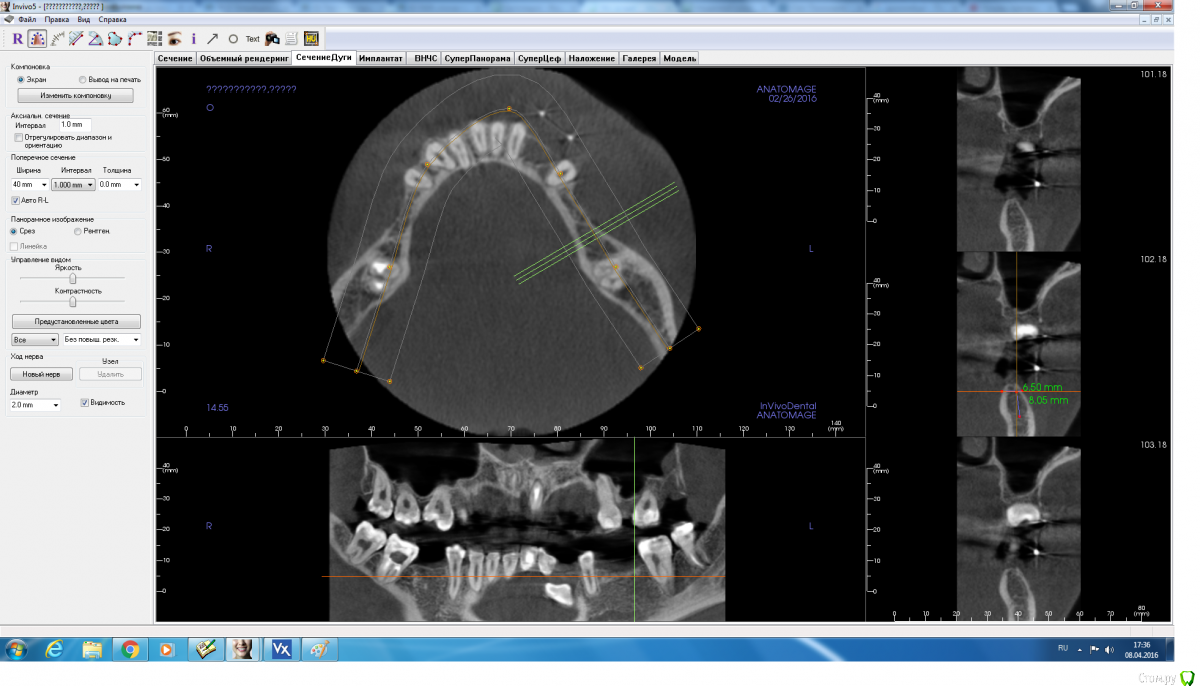

red_butler Опубликовано 8 апреля, 2016 Поделиться Опубликовано 8 апреля, 2016 срезы выставлены не корректно 2 Ссылка на комментарий

adamskot Опубликовано 8 апреля, 2016 Автор Поделиться Опубликовано 8 апреля, 2016 Момент, сейчас поправлюТак? Ссылка на комментарий

red_butler Опубликовано 8 апреля, 2016 Поделиться Опубликовано 8 апреля, 2016 Ред_бутлер, там же всего 10 мм от края гребня до канала? Куда заглубляться-то? Или ставить 3,5х8мм?С чего Вы взяли, конечно выставленные скрины полной информации не дают, но мне видятся 12-14 мм Ссылка на комментарий